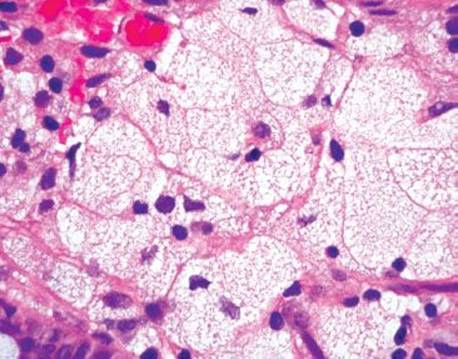

Figure 4.267 Muciphages. Higher power of previous image. Muciphages are histologically identical to foamy macrophages of any other site.

Figure 4.268 Muciphages.

Figure 4.269 Muciphages. Higher power of previous case shows the muciphages streaming through the superficial lamina propria.